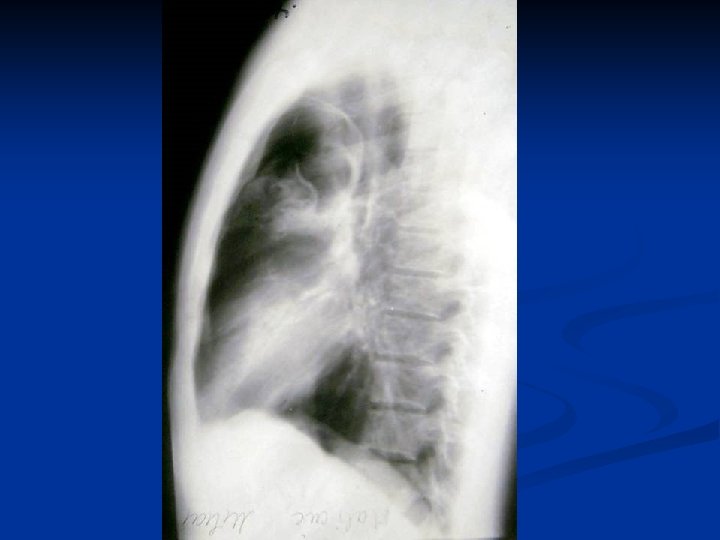

Metode de diagnosticare